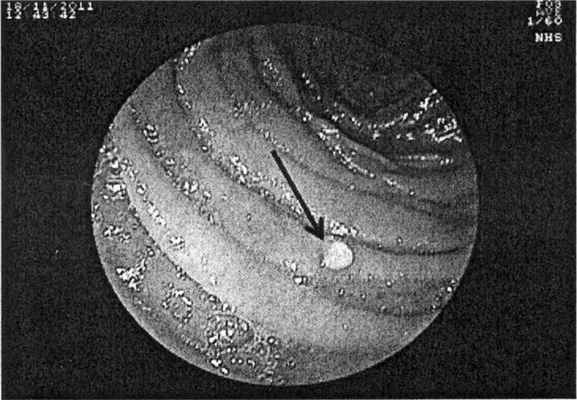

В нашем исследовании среди аденоматозных полипозных синдромов САП диагностирован у 3 больных, синдром Гарднера - у 2. Согласно классификации дуоденальных полипов Spigelman, у 2 больных имелась стадия 0, у 1 больного -II стадия и у 2 больных - III стадия заболевания. Аденома фатерова соска с дисплазией I-II степени выявлена у одной больной с синдромом Гарднера (аденома удалена эндоскопическим методом). Во время ДБЭ при стадии 0 по Spigelman в тонкой кишке визуализировались единичные (до 5 штук) плоские полиповидные образования (по данным гистологического исследования, гиперпластический полип с наличием лимфоидных фолликулов) (рис. 2, а). Рисунок 2. Эндофотография при ДБЭ. а - полип тощей кишки (указан стрелкой); б - множественные полипы тощей кишки (указаны стрелками).